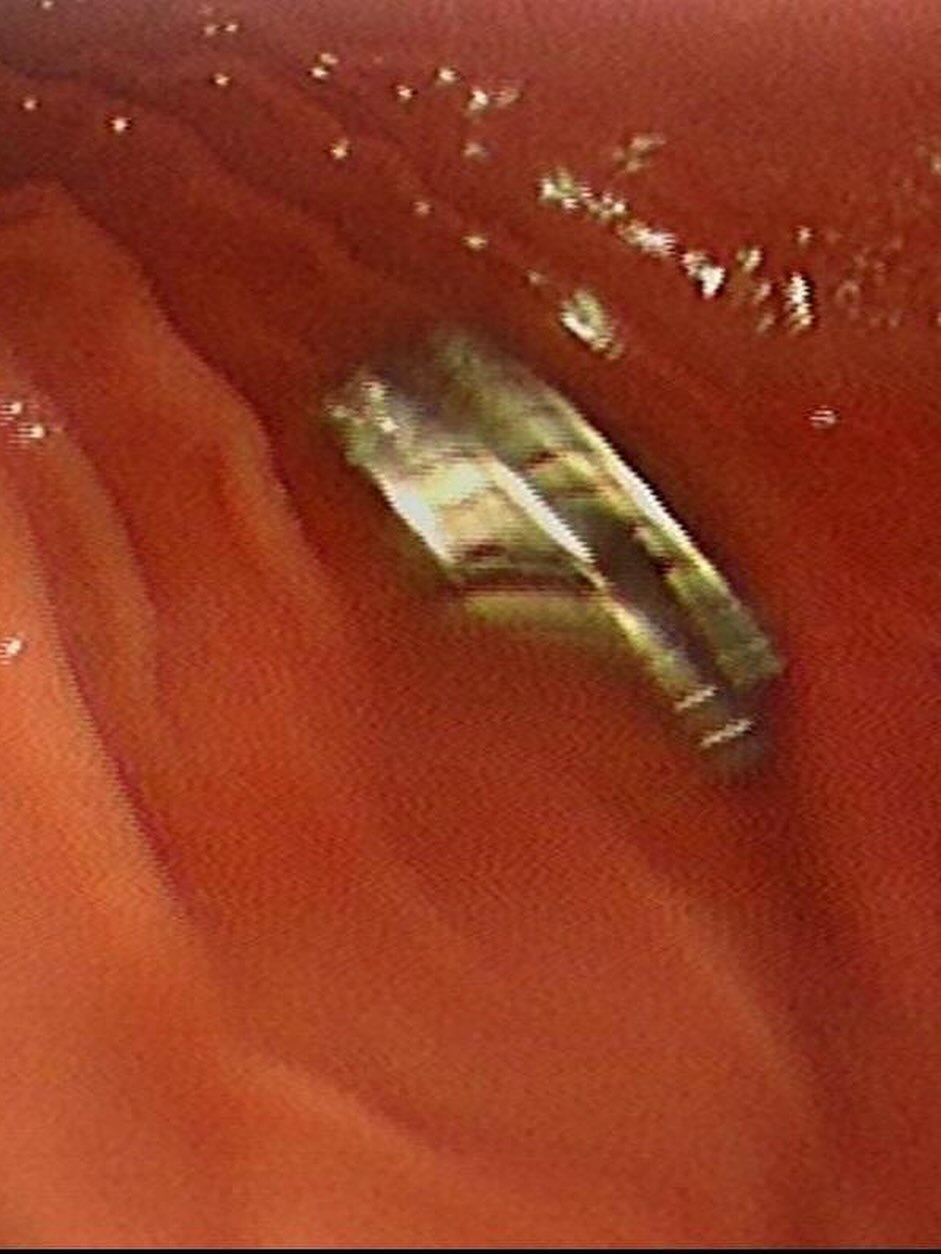

Fırat Üniversitesi Tıp Fakültesi Çocuk Gastroenteroloji, Hepatoloji ve Beslenme Bilim Dalı Başkanı Prof. Dr. Yaşar Doğan ve ekibi tarafından gerçekleştirilen operasyonla, çocuğun yemek borusuna yapışan 19 mıknatıs endoskopik yöntemle çıkarıldı.

Mıknatısların, mide girişinde ve yemek borusunda zedelenmelere yol açtığı belirtildi. Çocuk tedavisinin ardından taburcu edildi.